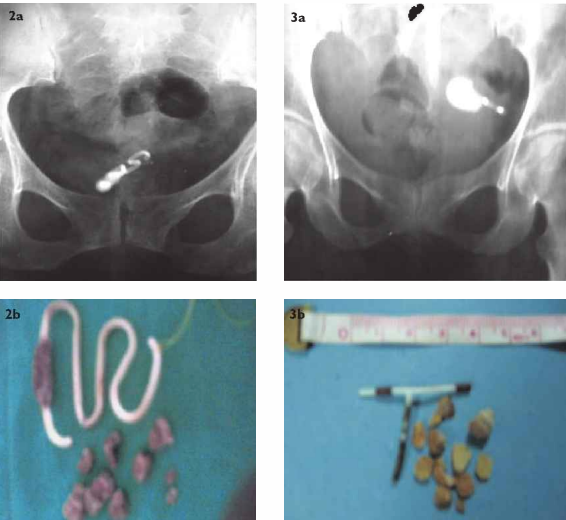

Intrabladder Device Gallery Intrabladder Device By Nicole Angemi|2025-09-15T14:50:36-04:00March 23rd, 2022|The Gross Room, MEDICAL, FREAK ACCIDENT, Foreign Bodies, Women's Health| Read More 23